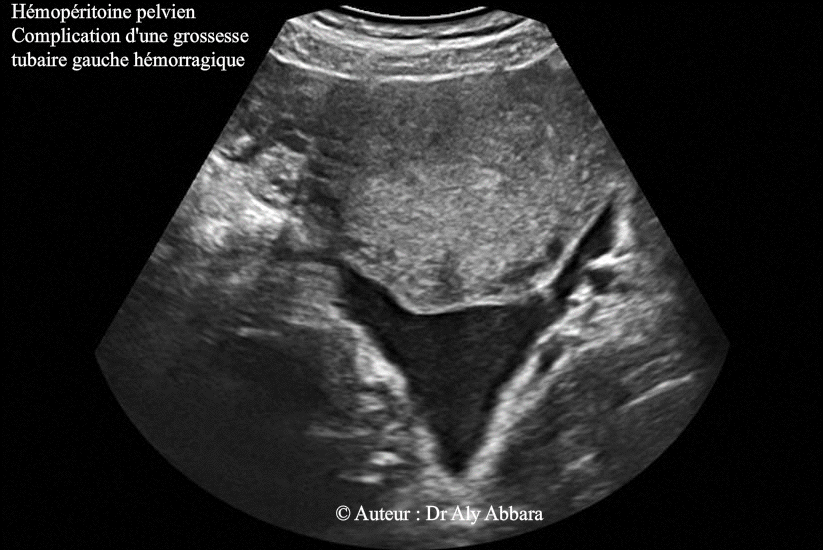

- Images échographiques montrant un hémopéritoine pelvien mis en évidence sur une coupe transverse et sagittale médiane de l'utérus ; il s'agit d'une hémorragie intra-abdominale étendue jusqu'à l'espace péri-hépatique (l'espace de Morison ou l'espace interhépatorénal) et due à présence, chez la patiente, d'une grossesse extra-utérine tubaire distale hémorragique.

Le dosage de β-hCG plasmatique était égal à 2400 UI/l.